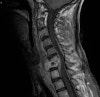

3. MRI

-

정확하고 빠른 효과적인 진단 수단

단, pyogenic과 non-pyogenic infection을 감별할 수 없으므로 조직 생검의 필요성을 줄이지는 못합니다.

추체와 그 사이의 추간강 부위는 T2 강조영상에서는 신호강도 증가, T1 강조영상에서는 신호강조 감소되어 경막 외 확장이나 연부조직 농양의 윤곽을 나타내는 데 유용합니다.

MRI : 척추 감염(Spinal infection)